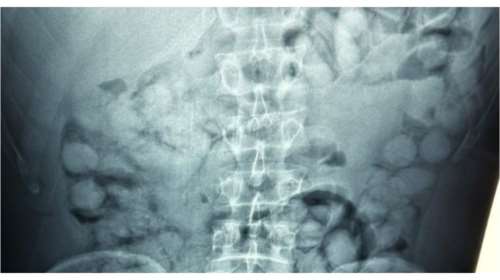

"Ελ. Βενιζέλος": Συνελήφθη Βραζιλιάνος που είχε καταπιεί 100 "αυγουλάκια" κοκαΐνης

Ο άνδρας έφτασε στην Αθήνα, μέσω Παρισιού και στον έλεγχο που διενεργήθηκε, διαπιστώθηκε ότι είχε καταπιεί περίπου 100 "αυγουλάκια" κοκαΐνης.